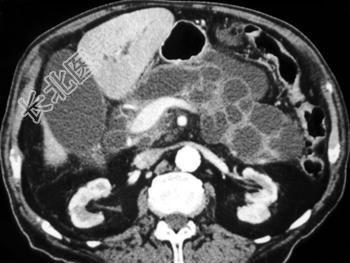

- 单项选择题根据所提供的图像,可除外下列哪种诊断 ( )

A、胰腺导管内乳头状黏液性肿瘤

B、胰腺囊腺瘤

C、胰腺假性囊肿

D、胰腺癌

E、以上都不是